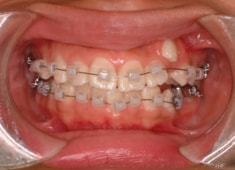

治療開始時

治療開始から5ヶ月後